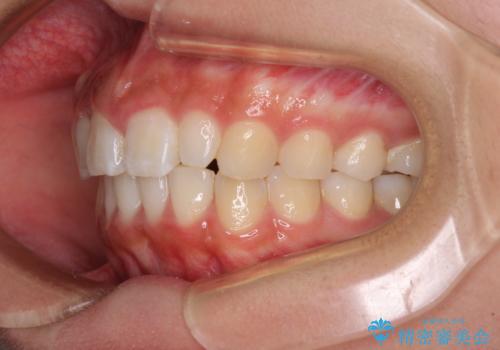

前歯のデコボコを治したい インビザラインによる矯正治療

- 前歯のデコボコ気になるとのことで来院された患者様です。

上下顎ともに歯列全体の後方移動とIPR(歯と歯の間を削る)によってデコボコが解消するように設計し、インビザラインにより治療を行うこととしました。

上顎左右前歯に矮小歯があるため、上顎の奥歯は下顎に対して相対的に前方に位置することになりました。

それでも奥歯の咬みにくさはなく、患者様には大変満足していただきました。